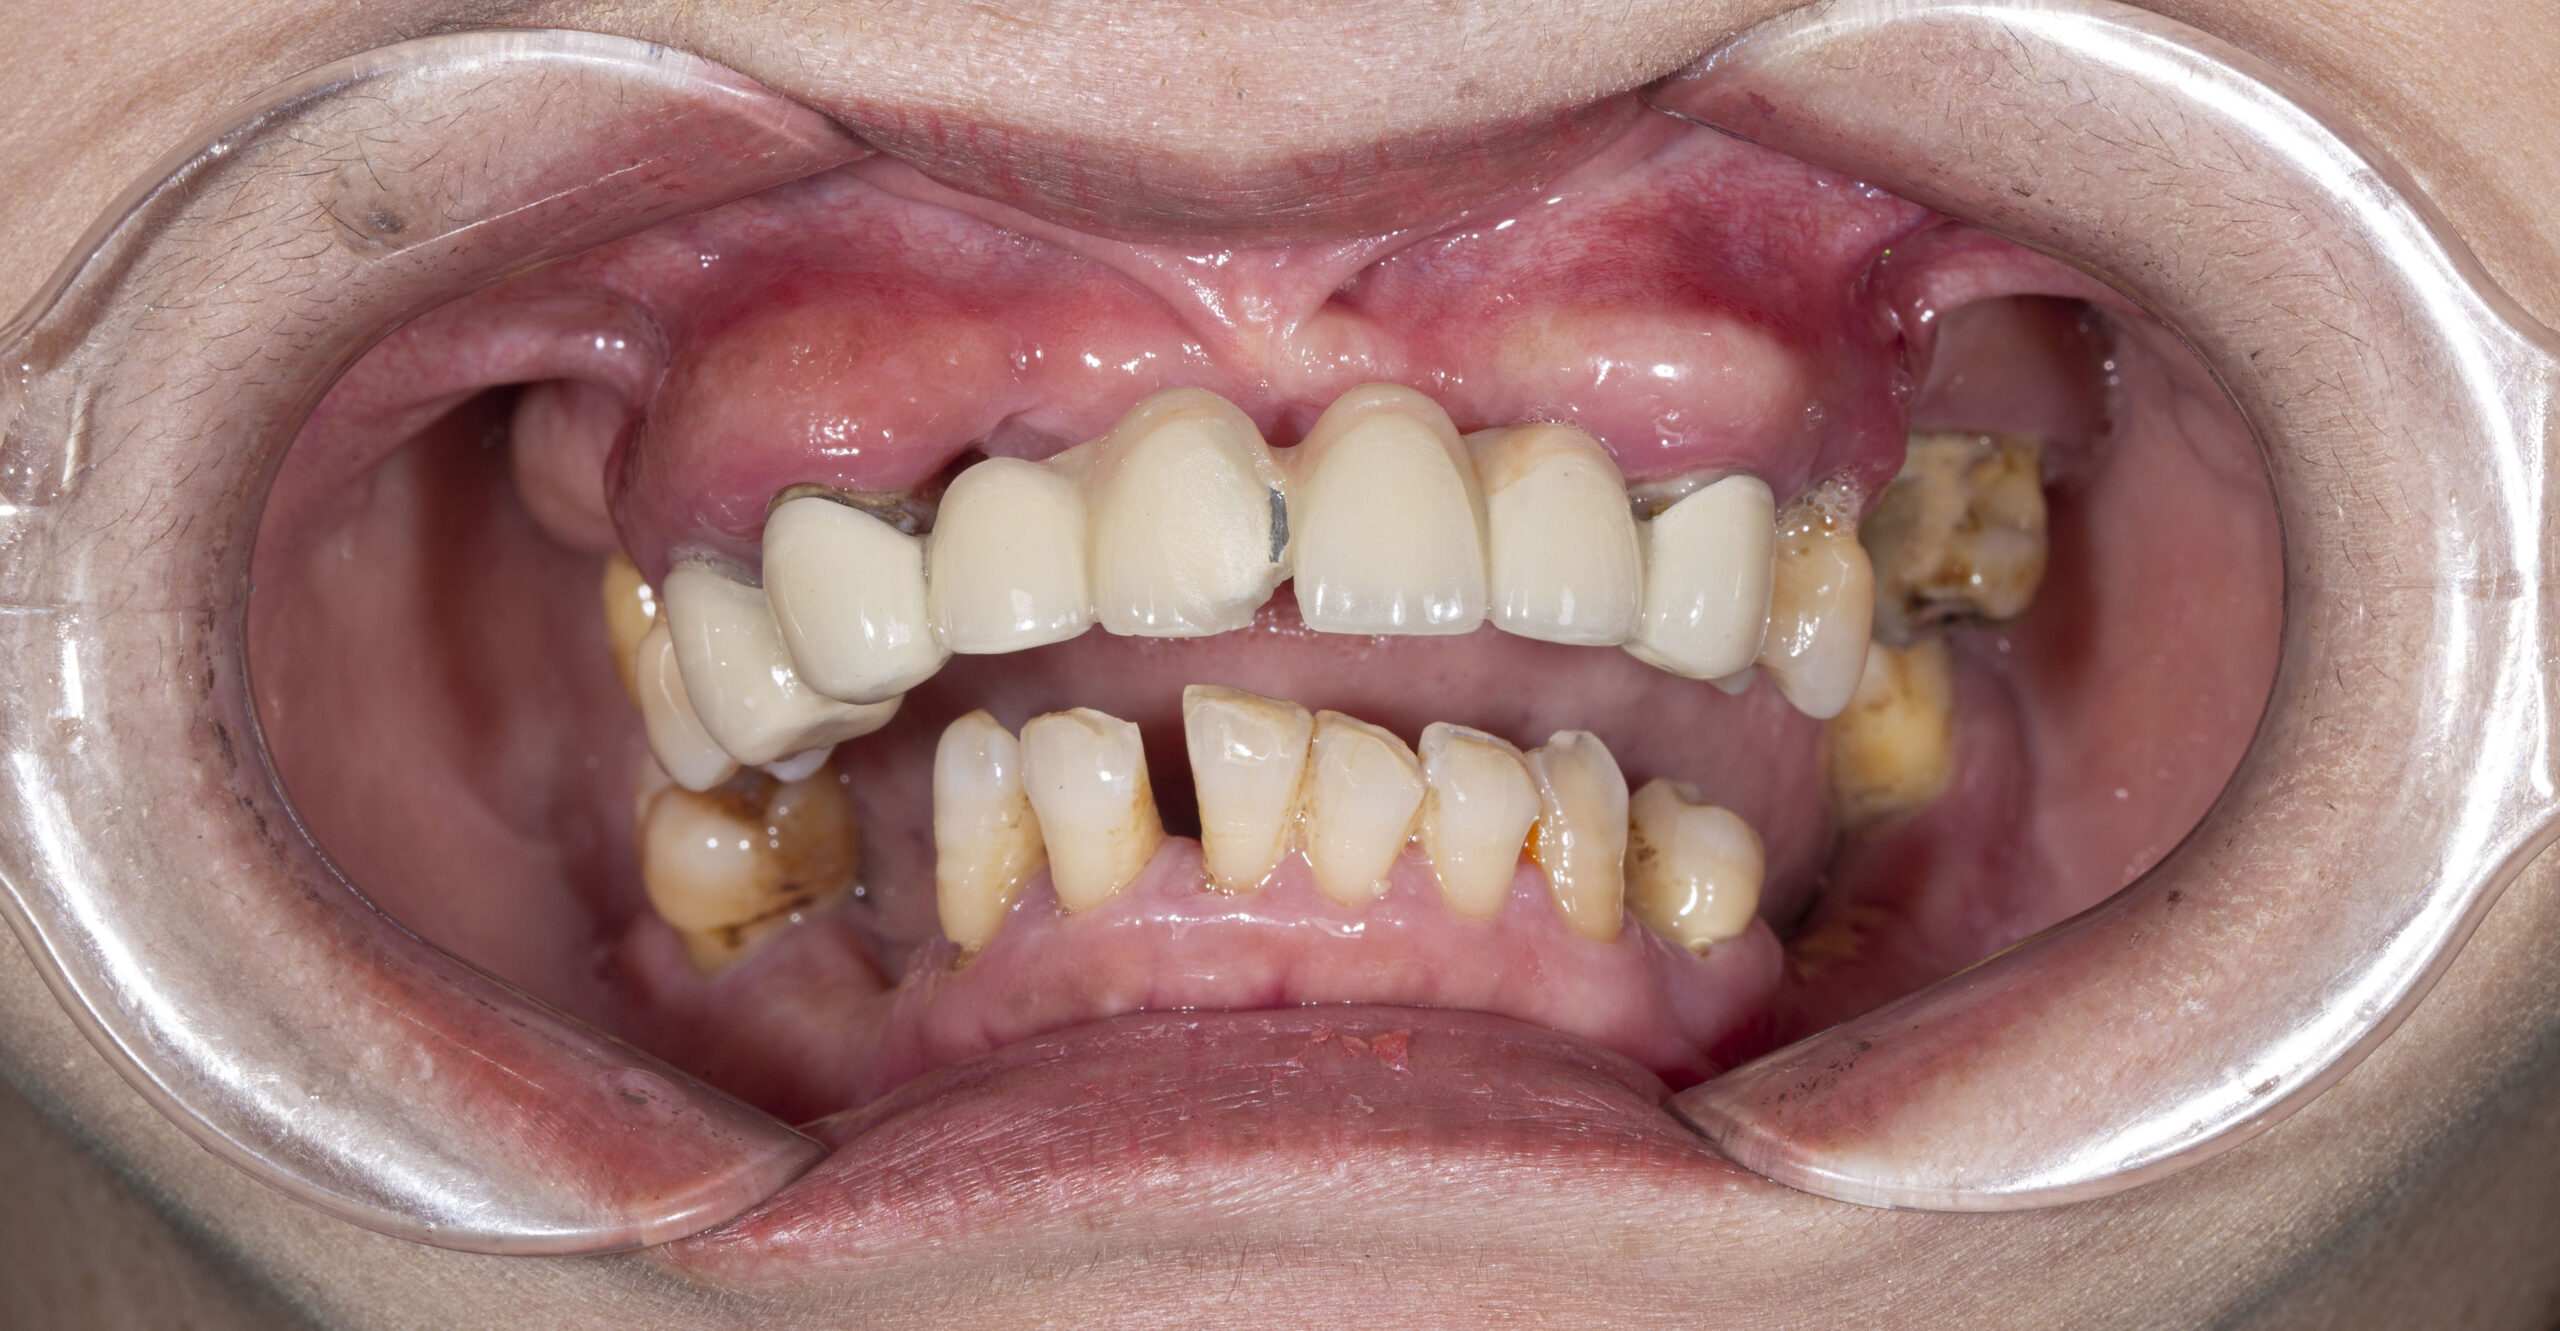

Cầu răng cũ của cô không chỉ hư hỏng chức năng mà còn ảnh hưởng lớn đến thẩm mỹ. Xương hàm tiêu nhiều, phần cầu răng bị tụt tạo ra khoảng hở lớn giữa lợi và răng giả – gọi là “gầm cầu”.

Những người gặp cô thường lầm tưởng cô đang mím môi hoặc không vui, bởi khi cười, răng không lộ mà lợi thụt sâu, tạo nên đường cười đảo ngược – một biểu hiện khiến gương mặt già nua hơn rất nhiều.

Hàm dưới cũng không còn răng ăn nhai

Không chỉ mất thẩm mỹ, cô Hằng còn mất hàng loạt răng ăn nhai chính ở hàm dưới. Việc ăn uống trở nên khó khăn – mỗi bữa ăn là một thử thách: